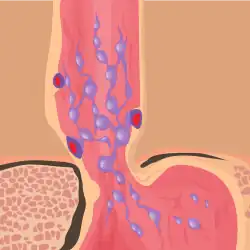

The upper two thirds of the esophagus are drained via the esophageal veins, which carry deoxygenated blood from the esophagus to the azygos vein, which in turn drains directly into the superior vena cava. These veins have no part in the development of esophageal varices. The lower one third of the esophagus is drained into the superficial veins lining the esophageal mucosa, which drain into the left gastric vein, which in turn drains directly into the portal vein. These superficial veins (normally only approximately 1 mm in diameter) become distended up to 1–2 cm in diameter in association with portal hypertension.

Normal portal pressure is approximately 9 mmHg compared to an inferior vena cava pressure of 2–6 mmHg. This creates a normal pressure gradient of 3–7 mmHg. If the portal pressure rises above 12 mmHg, this gradient rises to 7–10 mmHg.[5] A gradient greater than 5 mmHg is considered portal hypertension. At gradients greater than 10 mmHg, blood flowing through the hepatic portal system is redirected from the liver into areas with lower venous pressures. This means that collateral circulation develops in the lower esophagus, abdominal wall, stomach, and rectum. The small blood vessels in these areas become distended, becoming more thin-walled, and appear as varicosities.

In situations where portal pressures increase, such as with cirrhosis, there is dilation of veins in the anastomosis, leading to esophageal varices.[3] Splenic vein thrombosis is a rare condition that causes esophageal varices without a raised portal pressure. Splenectomy can cure the variceal bleeding due to splenic vein thrombosis.